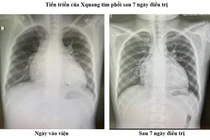

Bệnh nhi 11 tuổi bị suy tim cấp rất nặng, EF chỉ còn 18% vừa được Bệnh viện Đa khoa Xanh Pôn điều trị thành công.

Bệnh nhi nhập Khoa Nhi Tim Mạch và Khớp, Bệnh viện Đa khoa Xanh Pôn trong tình trạng suy tim cấp rất nặng, khó thở, men tim tăng, EF chỉ còn 18%.

Qua thăm khám, X-quang tim phổi, điện tâm đồ, siêu âm tim và xét nghiệm men tim, các bác sĩ xác định đây là bệnh cơ tim giãn - nguyên nhân hàng đầu gây suy tim mạn ở trẻ em, tiên lượng nặng. Căn bệnh này có thể do đột biến gen (30–50%), rối loạn chuyển hóa (acid béo, ty thể, glycogen), thiếu vi chất (Thiamin, Selenium, Carnitine), nhiễm độc chất/thuốc (doxorubicin, cyclophosphamide) hoặc sau viêm cơ tim.